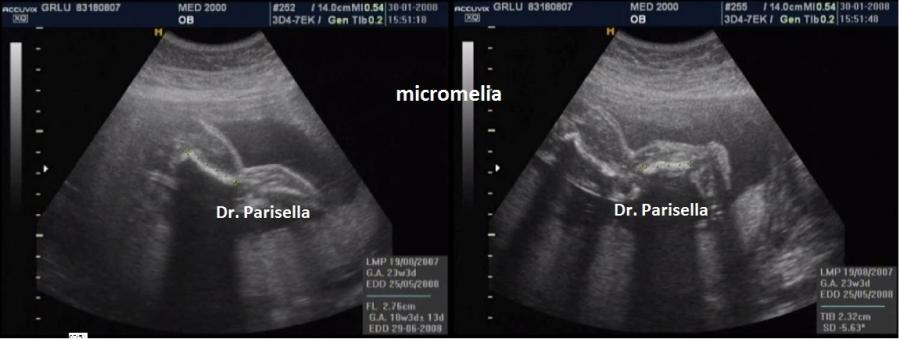

Quella che interessa dal punto di vista della diagnosi ecografica prenatale è l'Osteogenesi Imperfetta tipo II (OMIM 166210) caratterizzata da fragilità ossea con fratture multiple, micromelia severa dovuta alle fratture delle ossa lunghe, ipoplasia toracica severa a volte con fratture costali, ipomineralizzazione diffusa del cranio.  Ecograficamente si manifesta con ossa corte, ricurve e fratturate (le ossa fratturate si presentano angolate); ossa craniche scarsamente ossificate (tanto che la volta cranica può avere una ecogenicità simile a quella della linea mediana) con conseguente migliore evidenza e definizione delle strutture cerebrali e segno caratteristico la deformabilità della teca cranica.;  ipoplasia toracica con fratture costali; IUGR; movimenti fetali scarsi.